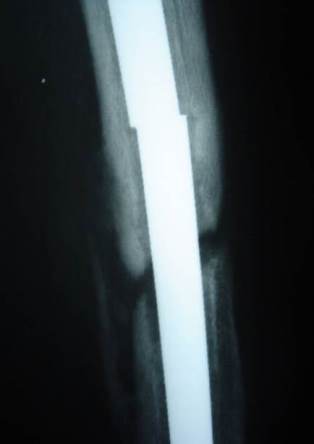

A few months later the patient presented with 2 nail breaks.

Nail parts after removal

Middle part of the nail was removed by a small break in the lateral cortex.

Distal part of the nail was removed by a hole distally in the lateral cortex then pushed by a drill pit and pulled through the medulla by an intestinal clamp.